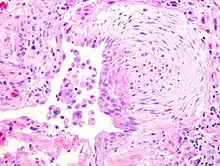

![]() | Granulation tissue | Micrograph showing proliferating capillaries, fibroblasts and acute inflammatory cells. | Category: Histopathology of granulation tissue | Granulation tissue |